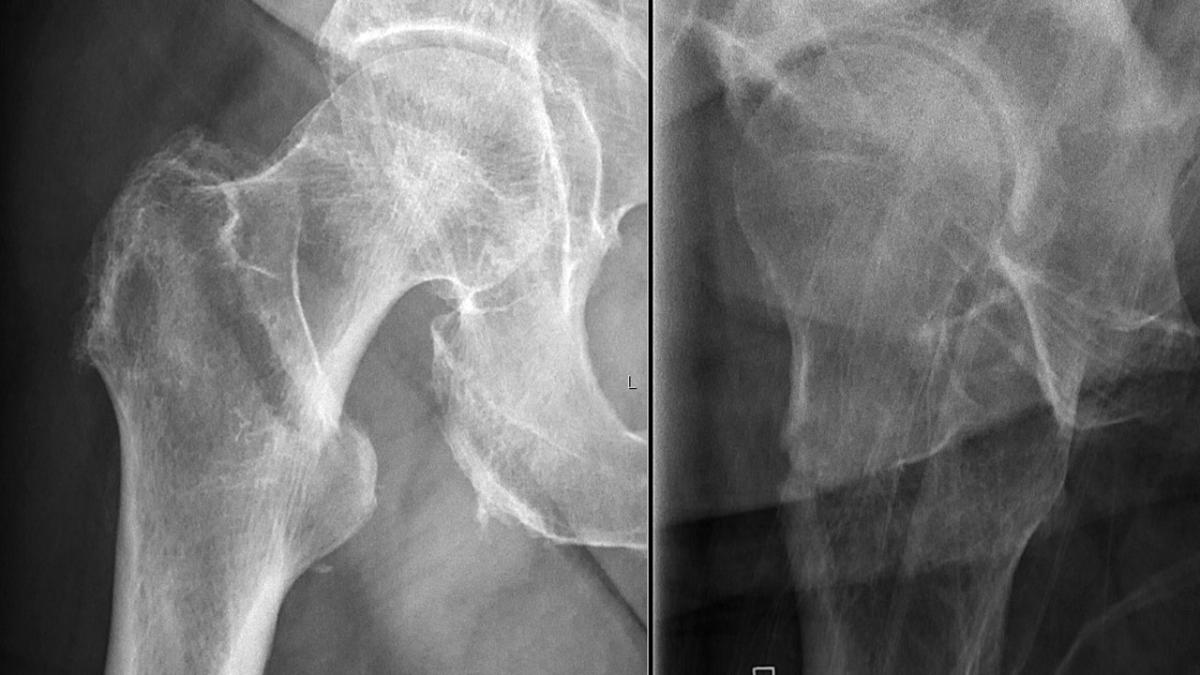

Перелом шейки бедра